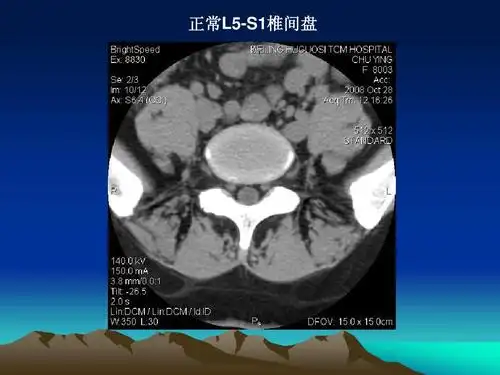

腰椎ct诊断ppt